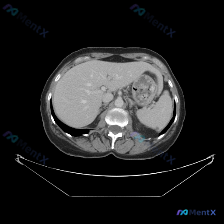

今天看到一张很有意思的上腹部CT软组织窗图像,预设的问题是“找脾脏病变”,但整理完思路发现,这个病例的重点反而不在预设方向上。 --- 先整理一下图像里的客观信息 基础评估 图像质量清晰,对比度适中,无明显运动伪影,层面在上腹部,能看到肝、胃、脾、胰、双肾、腹主动脉这些结构。 各脏器表现 1. 脾脏...

看到一份挺有意思的资料,是关于“脾脏病变”的读片,但看完影像分析后发现情况和预设不太一样,整理一下思路和大家分享。 病例核心影像信息 这是一份单幅腹部CT横断面软组织窗图像的分析: 1. 各实质脏器表现: - 肝脏:密度均匀,边缘光滑,无局灶性占位,肝门部结构清晰,无血管或胆管扩张。 - 脾脏:形态...

今天整理了一个很有意思的「反向思维病例,不是教大家怎么「找病」,而是教大家怎么「信没病」。 --- 先看基本情况 预设疑问: 图像中观察到的具体异常是什么?脾脏病变 影像资料: 单张腹部增强CT(轴位软组织窗)+ 正式影像分析报告 --- 关键影像所见(严格基于报告) 这份正式影像分析是这么说的:...